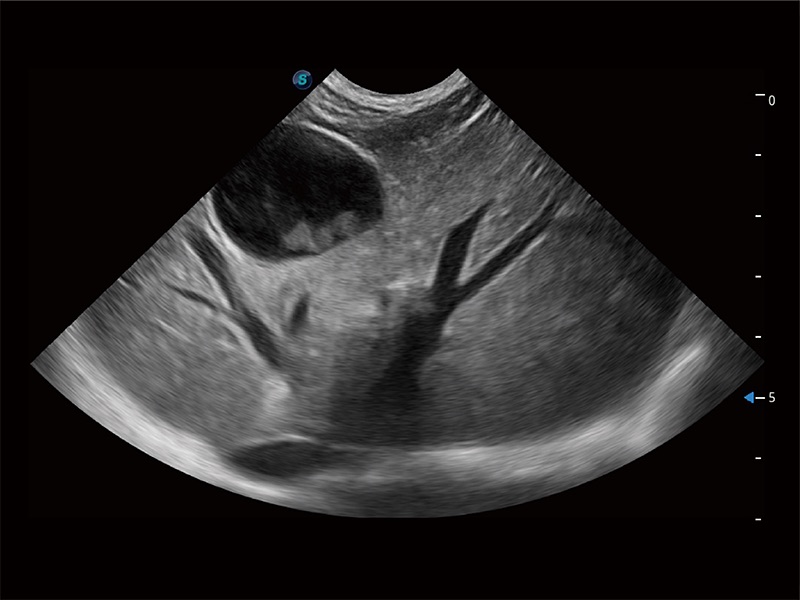

ProPet 80 专为动物医生设计,对不同的动物体型和生理结构作出了针对性的优化。通过动物影像专用软件,可满足个性化的应用需求,帮助动物医生获得更精确的诊断数据。

为精细结构及组织边缘提供高清晰度的图像和更大的成像视野。帮助减轻医生的用眼疲劳,快速精准获得测量的数据。

针对宠物、马科、农场动物、实验室动物和异宠等20多种动物种类,预置丰富的动物注释及动物体标库。